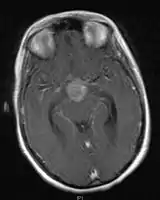

- Mainly located in midline structures, suprasellar region or pineal gland, also basal ganglia and hypothalamus

- Pineal Gland Germinoma

- Suprasellar Germinoma

- Toronto; 2006 (1995-2004) PMID 16530340 -- "Limited-field radiation for bifocal germinoma." (Lafay-Cousin L, Int J Radiat Oncol Biol Phys. 2006 Jun 1;65(2):486-92.)

- Retrospective. 6 patients with bifocal germinoma (pineal + suprasellar). All with diabetes insipidus at presentation. Treated with chemo followed by limited-field RT (whole ventricle 24-40 Gy +/- boost). Median F/U 4 years

- Outcome: 100% complete remission

- Conclusion: Bifocal germinoma can be considered locoregional rather than metastatic disease